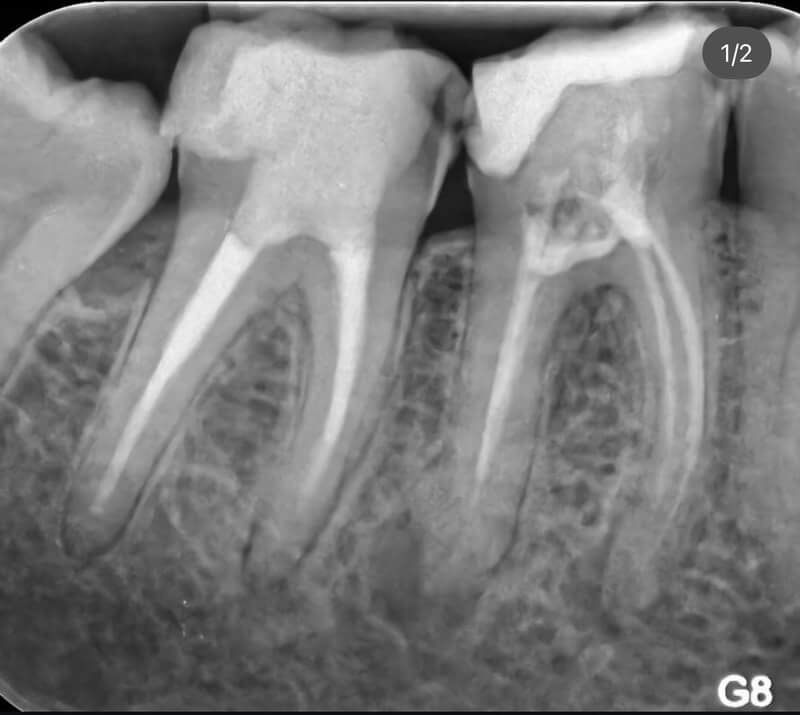

Endodonția este o ramură esențială a stomatologiei, axată pe diagnosticarea, prevenirea și tratamentul afecțiunilor pulpei dentare și a țesuturilor periapicale. Această specialitate joacă un rol crucial în salvarea dinților naturali, evitând extracțiile și menținând sănătatea orală pe termen lung. Prin tehnici avansate și echipamente de ultimă generație, endodonția asigură tratamente precise și eficiente, contribuind la redarea sănătății și funcționalității dinților într-un mod durabil și predictibil.